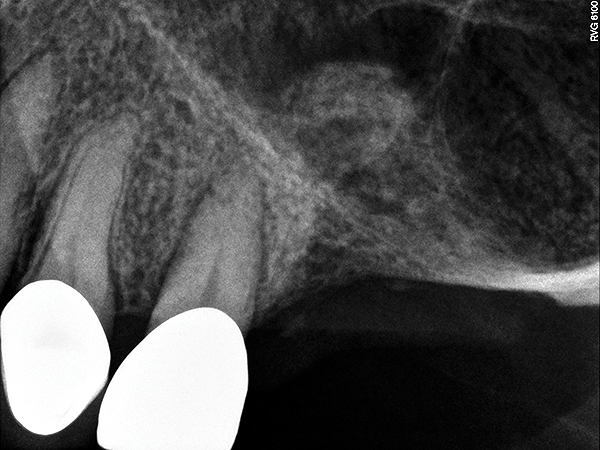

Fig 13. Case 1. Preoperative radiograph showing a ridge height of about 2 mm to 3 mm in the No. 14 position.

Figure 13